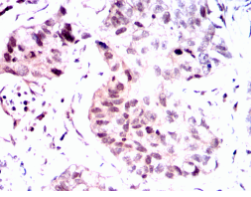

Immunogen:    Purified recombinant fragment of PGR (aa731-909) expressed in E. Coli.

IHC    1/200 - 1/1000